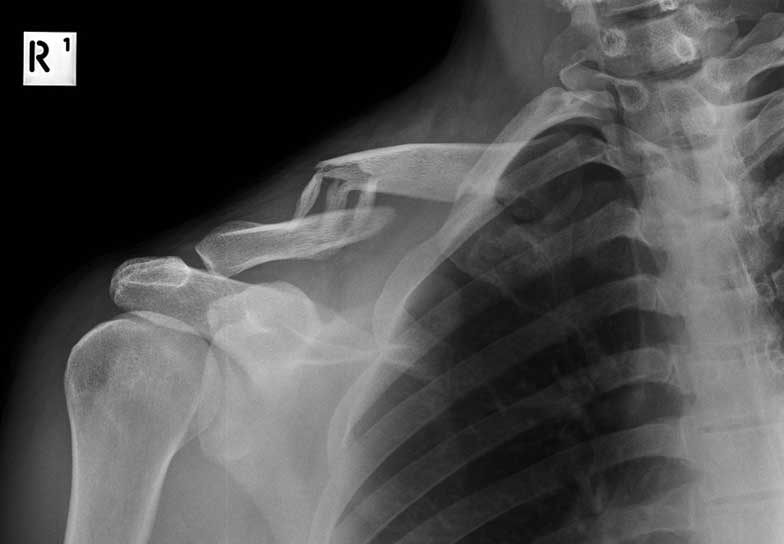

What do clavicle fractures look like on X-ray?

Below are examples of typical fractures that benefit from surgery.

Click an image to enlarge